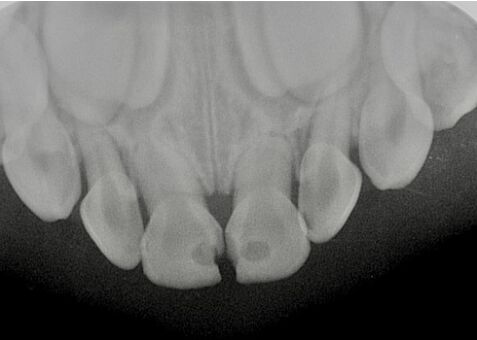

40.3歲男童因牙齒缺損及變色前來求診,拍攝放射線影像如圖示,下列敘述何者正確? (A)左側上顎正中乳門齒發生牙根內吸收 (B)左側上顎正中乳門齒牙冠應呈粉紅色 (C)此案例牙根吸收的原因可能是外傷 (D)此案例的診斷為根管堵塞(obliteration)